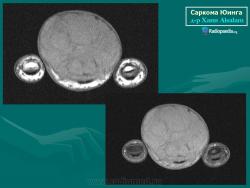

С Радиопедии.

Саркома Юинга грудной стенки.